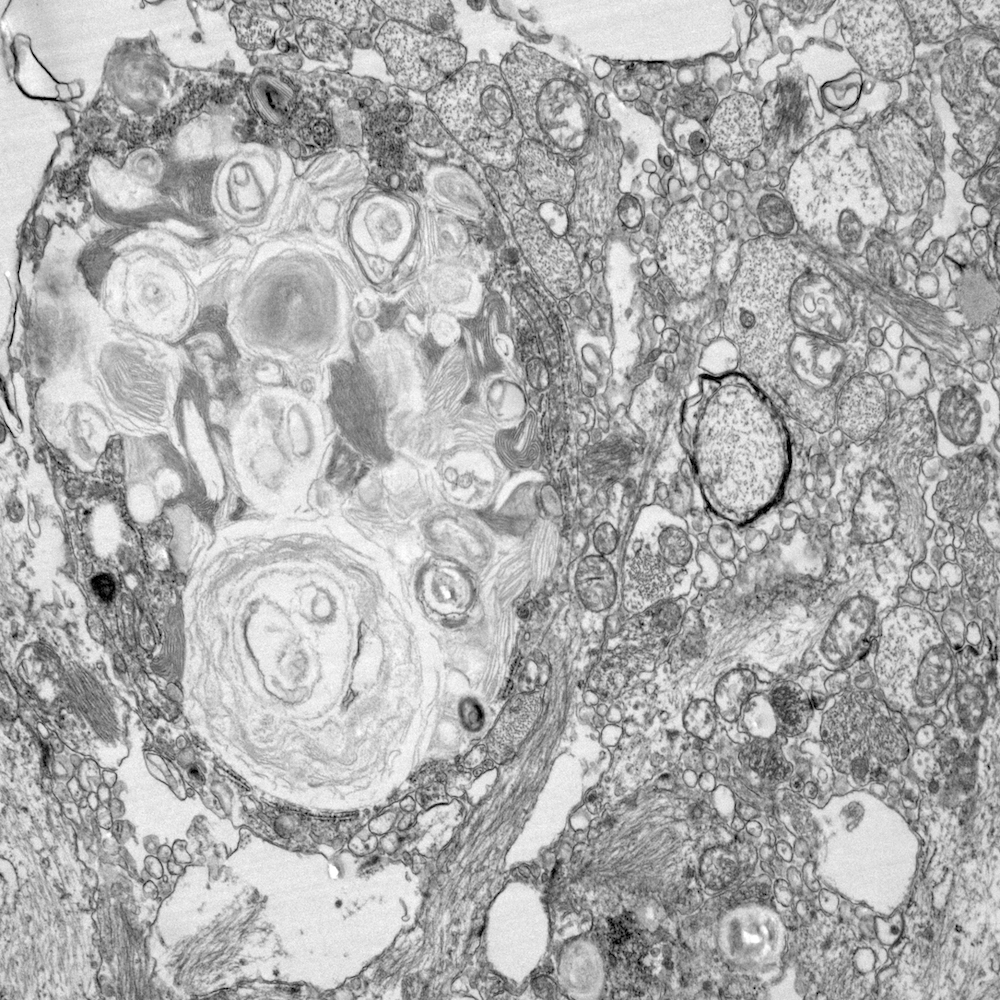

We study how glial cells and their networks keep the brain healthy—and what happens when these systems break down in development, aging, and inflammation. Right now, we are investigating how white matter dynamics shape glial function in preclinical models of multiple sclerosis. Combining neuroimaging, digital histopathology, and spatial omics to perform cross-species comparisons, we aim to uncover the mechanisms that drive myelin damage and repair, paving the way for better diagnosis and treatment of brain disorders.